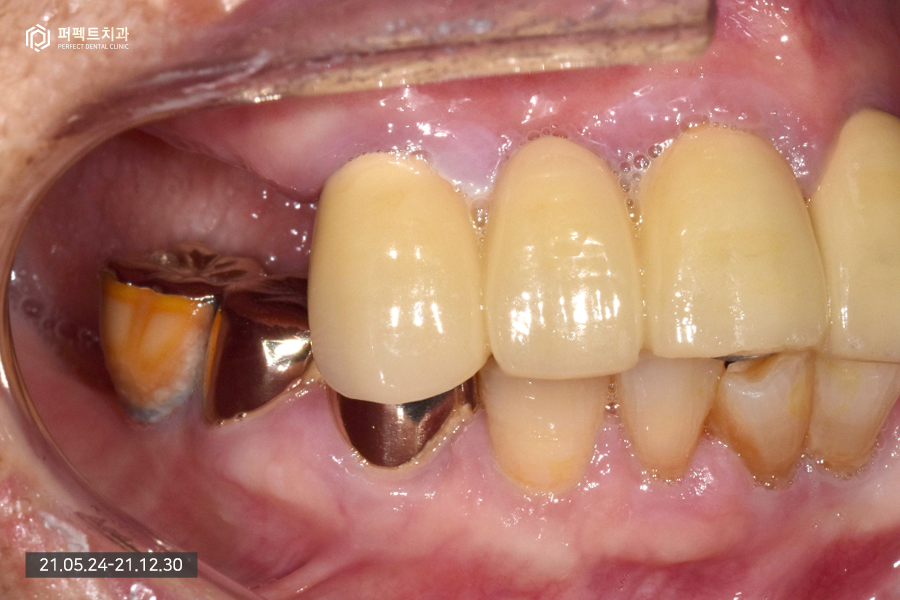

내원 당시 초진 사진입니다.

80대 여성 환자분으로 연세가 많은 편이셔서 앞니는 몇 개 남지 않았고 어금니는 아예 없는 상태였습니다.

남아있는 앞니의 경우 3개가 남아있고 하나는 걸어서 사용하고 있는 상황이었는데 앞니가 심하게 흔들리고 있는 상황이라 모두 발치 하기로 결정을 하였습니다. 이런 경우 윗니는 치아가 하나도 없는 상태가 되어 전체 임플란트로 수복하게 됩니다.

아래 치아의 경우 멀쩡한 것처럼 보이지만 실제로는 그렇지 않습니다. 발치를 해야하는 치아들도 있고 치아가 없는 부분은 임플란트로 수복하기로 하였습니다.